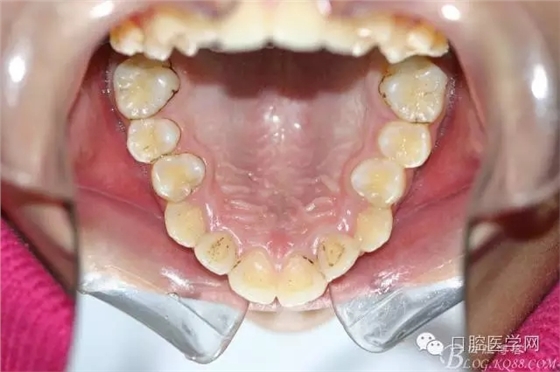

正畸查:替牙合。第一恒磨牙中性合。上牙弓尖圓型下牙弓方圓型。前牙覆合3度覆蓋7.5mm。下前牙咬到上舌側(cè)牙齦。上頜擁擠4.0mm,下頜擁擠

3.0mm。上頜稍前突下頜后縮,上下唇前突,上前牙覆蓋下唇,下唇外翻。面下三分之一過短,頦唇溝明顯,開唇露齒,頦饜窩明顯。顳下頜關(guān)節(jié)開閉口無彈響,無壓痛,開口型開口度正常。

正畸后照片: